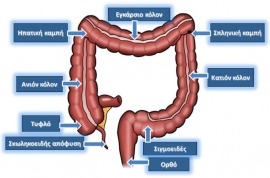

Τμήμα του παρακάτω ενημερωτικού κειμένου δημοσιεύθηκε για πρώτη φορά στο περιοδικό ΙΑΤΡΙΚΟΣ ΚΟΣΜΟΣ (2004, Περίοδος Β, αρ. Τεύχους 17) από τους Γ. Θεοδωρόπουλο και Κ. Κωνσταντινίδη ΤΙ ΕΙΝΑΙ ΤΟ ΠΑΧΥ ΕΝΤΕΡΟ; Προκειμένου να κατανοήσει κανείς την εκκολπωμάτωση, είναι αναγκαίες απλές γνώσεις της ανατομίας και λειτουργίας του παχέος εντέρου. Το…